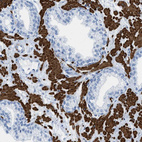

Immunohistochemistry analysis in human heart muscle and liver tissues using HPA018803 antibody. Corresponding DES RNA-seq data are presented for the same tissues.